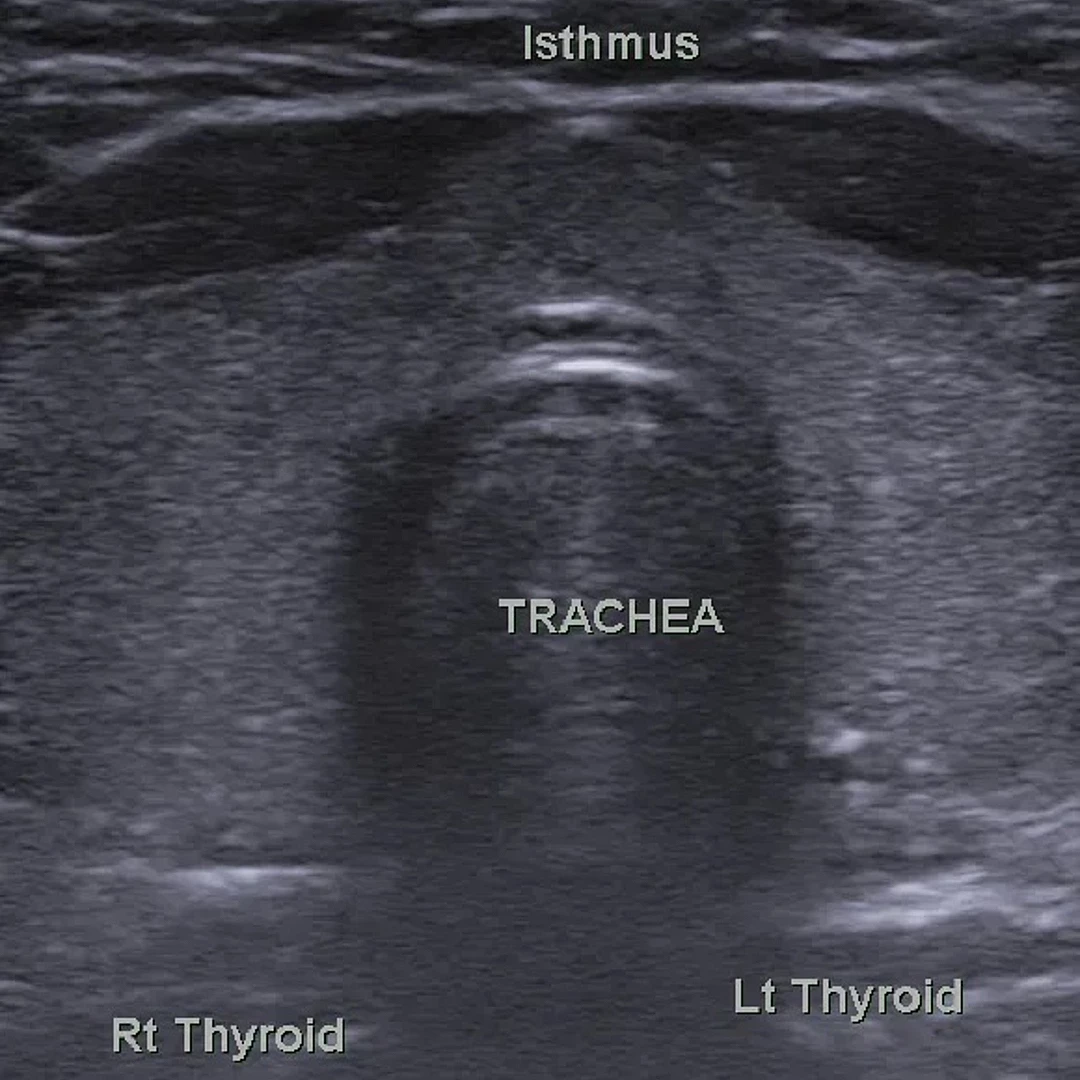

Thyroid and Neck Ultrasound

Thyroid and Neck Ultrasound provides detailed imaging of the thyroid gland, lymph nodes, and surrounding neck structures. It’s a safe, non-invasive method for detecting nodules, cysts, or other abnormalities.